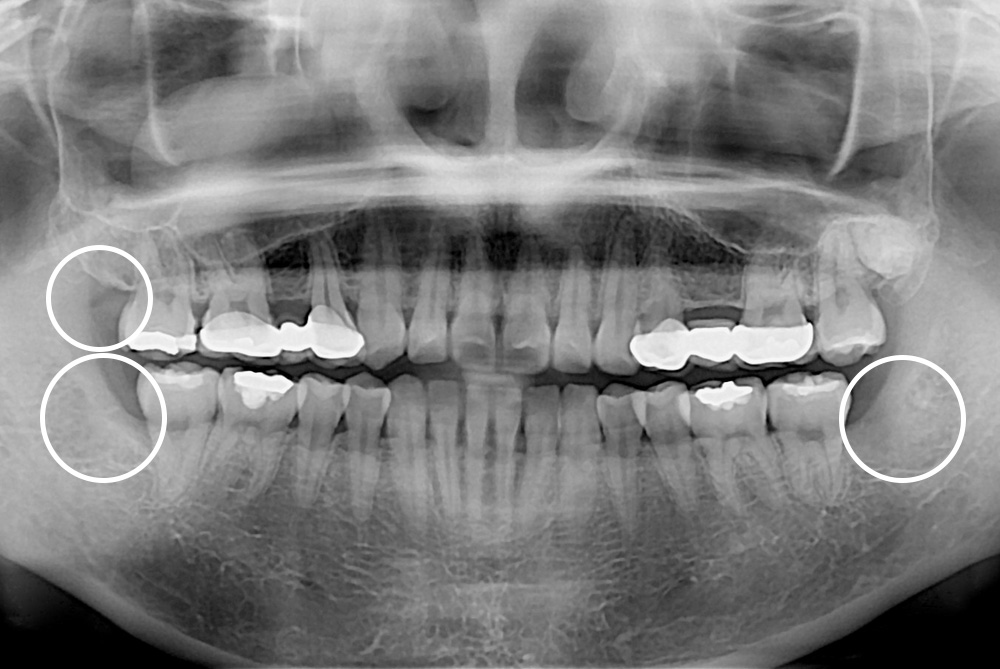

[사랑니] 매복 사랑니 발치

치료전 : 2019-08-14